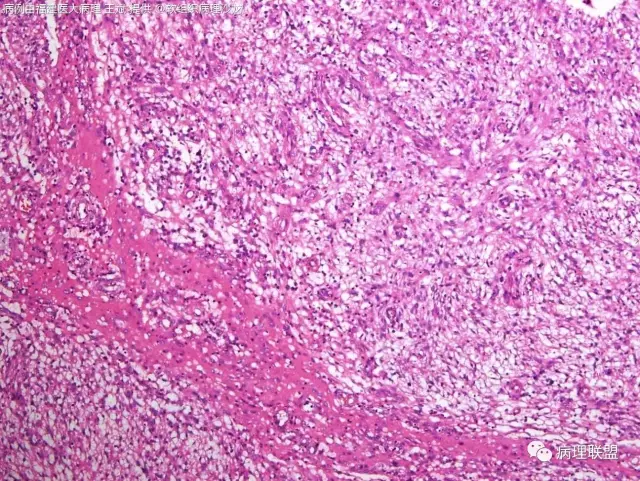

38岁,女性,手部小指背侧皮下肿物,3×2cm(病例由福建医大病理 王斌提供,致谢!)

血管瘤样纤维组织细胞瘤的肿瘤周围有淋巴细胞鞘,结节状分布,有假包膜,出血囊性变的为其主要特点,当然少数病例可以没有出血囊性变却出现粘液变。肿瘤细胞有一定异形性,属于低度恶性或交界性,最好做个FISH,看看有没有EWSR1-CREB1融合基因,刚查了一下,血管瘤样纤维组织细胞瘤还有另一种EWSR1-ATF1融合基因,无论是哪种,用EWSR1分离探针就可以检测